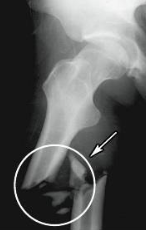

potts fracture